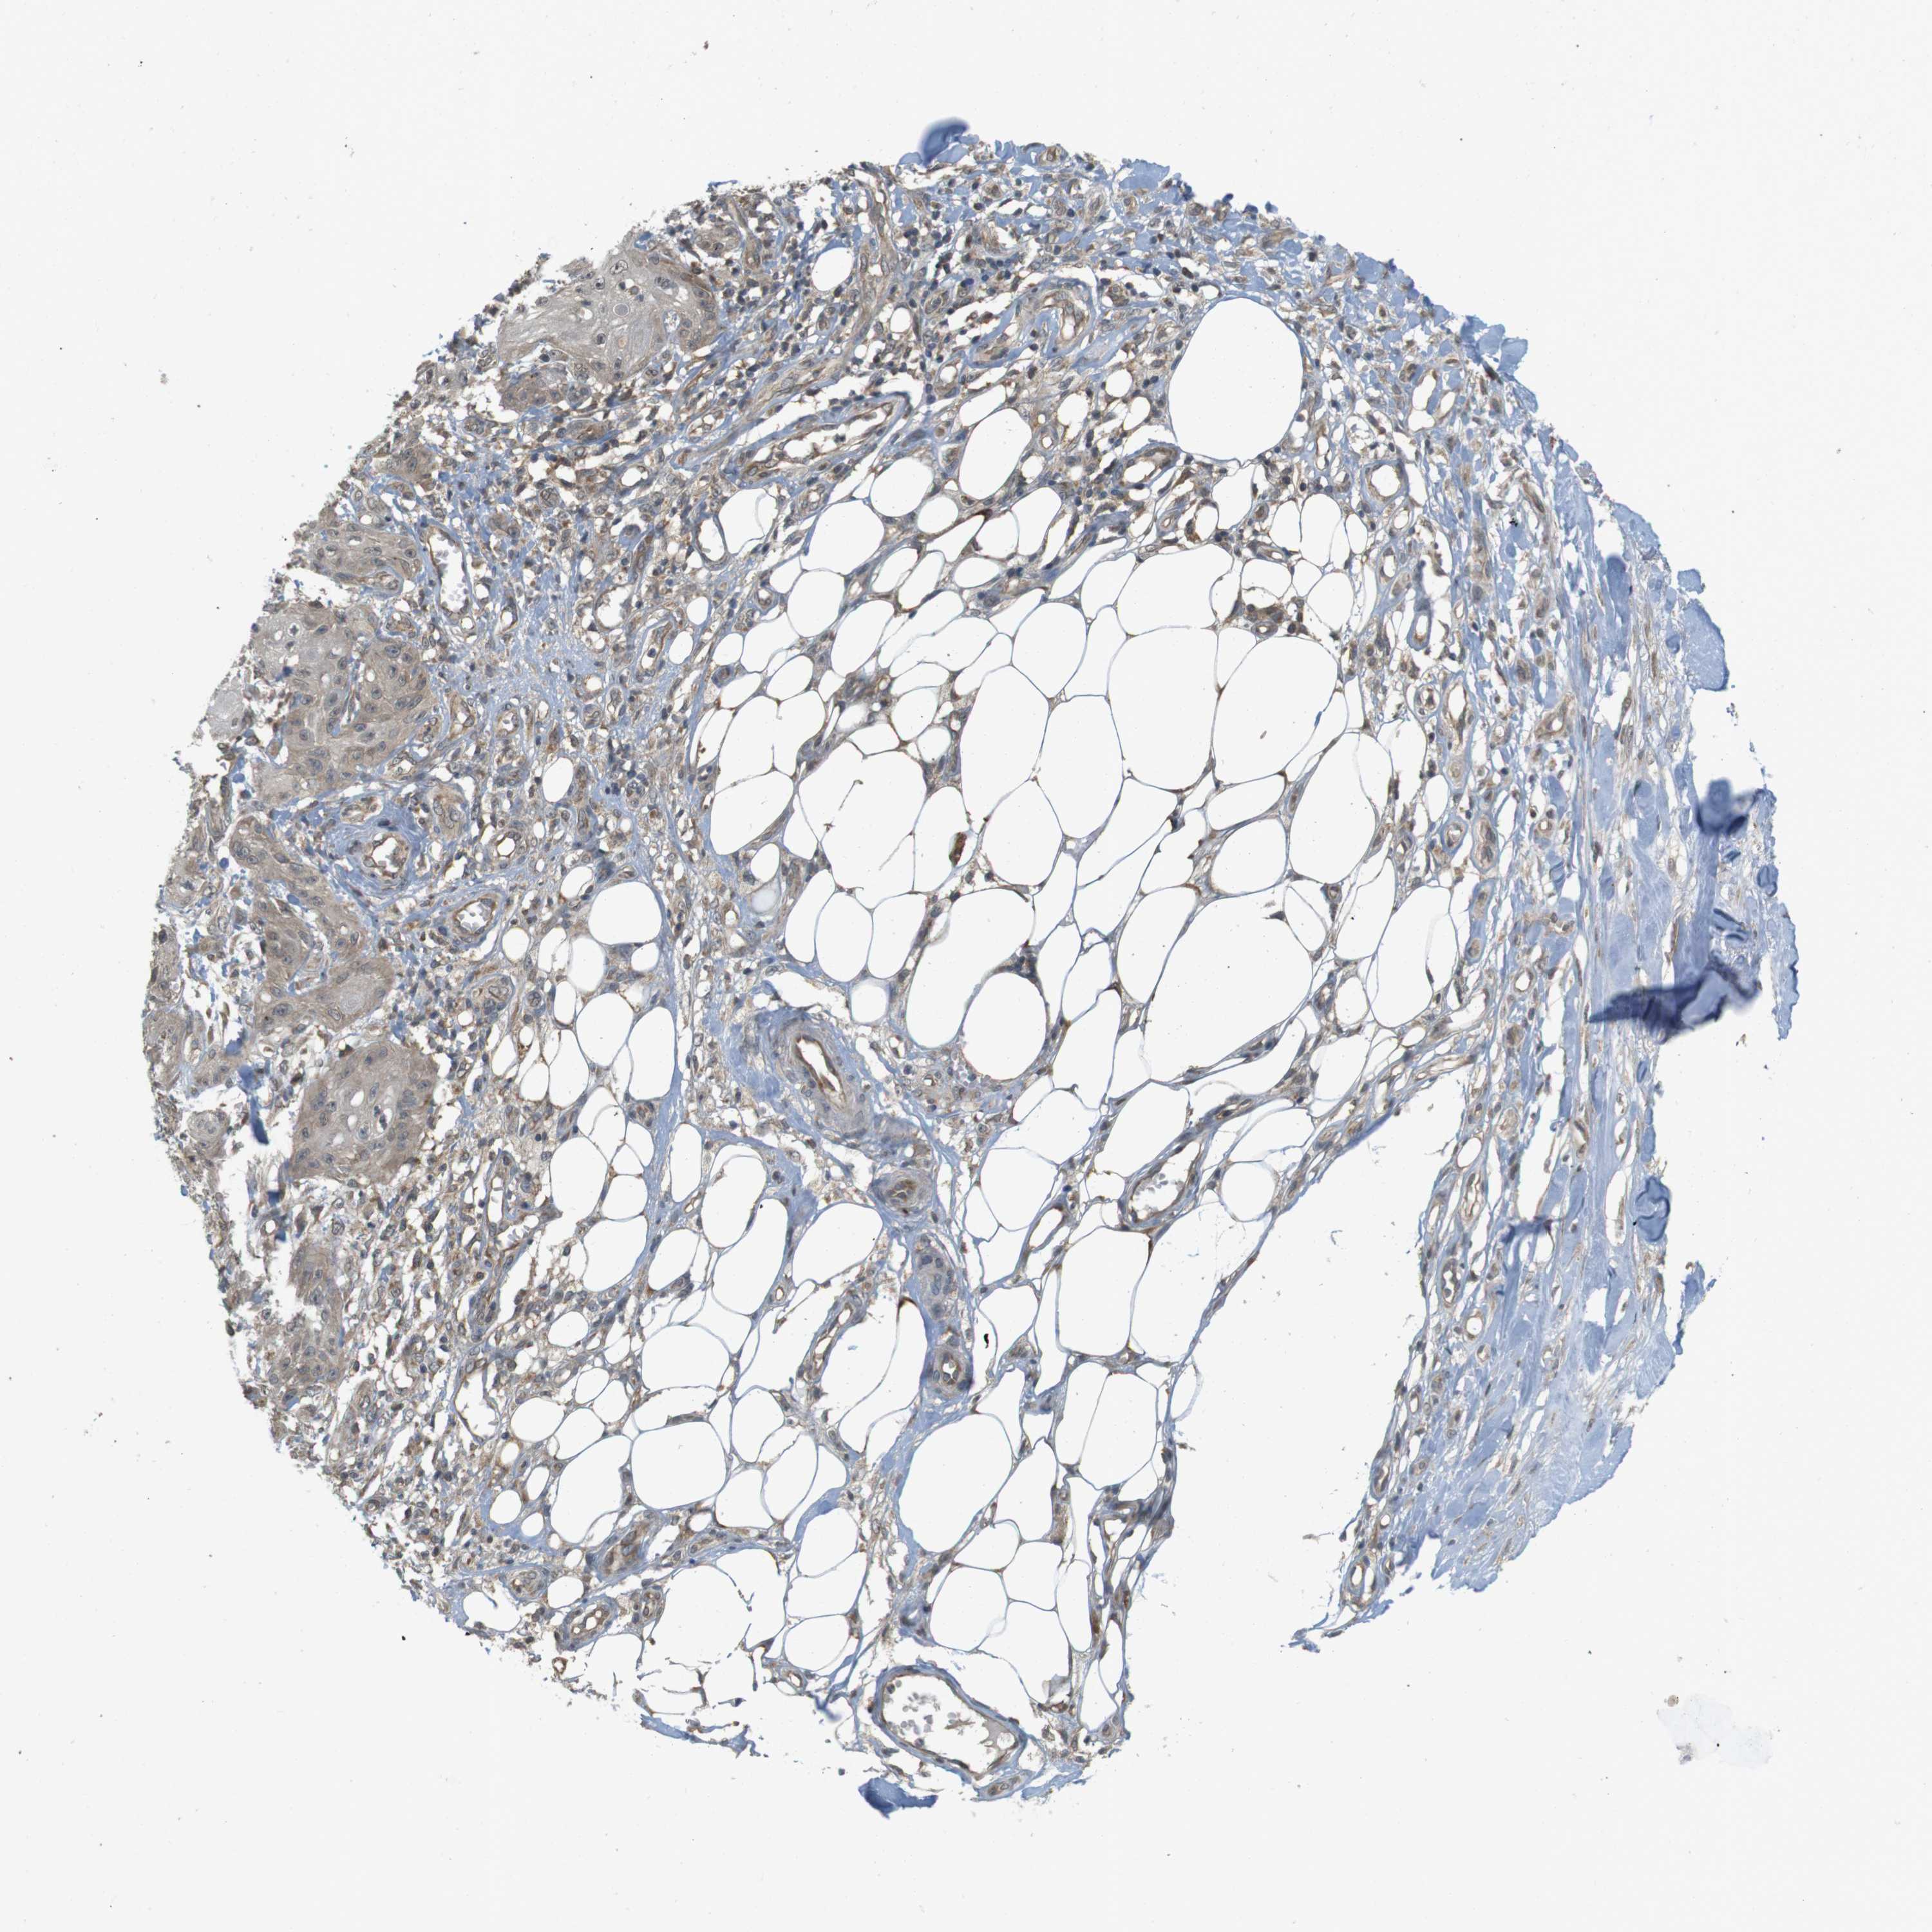

SKIN CANCER

Basal cell and squamous cell cancer